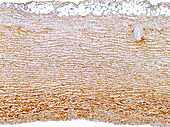

13613516 - Vein adventitia, light micrograph